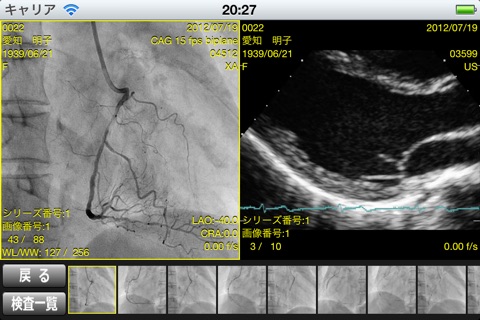

マルチフレームDICOM PACS日本国内トップシェアのGOODMANが、iPad専用のビューアーをリリースしました!

・MultiFrame DICOM画像をダウンロード、閲覧することが出来ます。

・横向きにした場合の2分割表示

・同一患者の別検査リスト表示